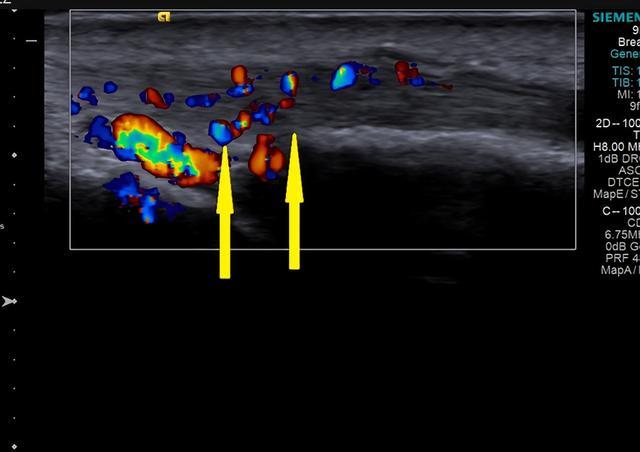

彩色多普勒超声显示:增厚的肌腱及腱鞘血流信号增多。